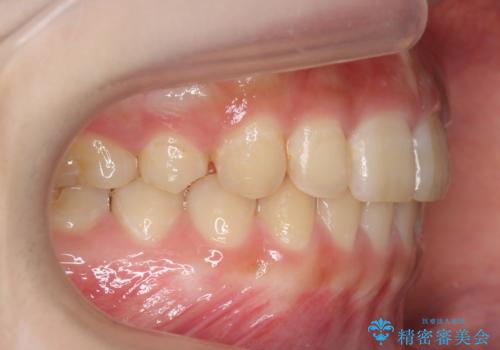

前歯のがたつき 過蓋咬合

今回は上の前歯が内側に傾いている症状があり(Angle Ⅱ級2類)、その修正に時間がかかっています。

奥歯のかみ合わせが、歯と歯が向かい合わせになっておりまた、歯ぎしりも多い方で装置の脱離も頻繁にありました。